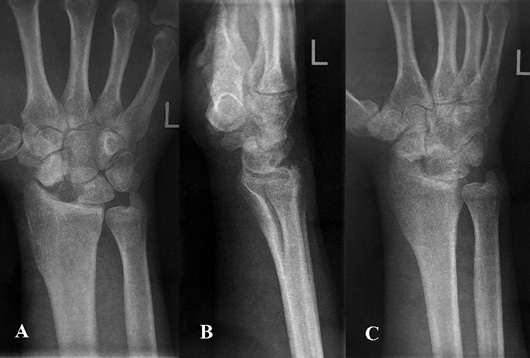

2 pav. Kairiojo riešo trijų krypčių rentgenogramos po operacijos: priekinė rentgenograma (A), šoninė rentgenograma (B), įstrižinė rentgenograma (C)

Operacijos metu atliktas pjūvis kairiosios plaštakos nugariniame paviršiuje tarp trečiojo ir ketvirtojo tiesiamųjų sausgyslių kompartmento laivelio projekcijoje. Naudojant bukąją ir aštriąją disekciją, pasluoksniui pasiektas kaulas. Rastas nesugijęs laivelio lūžis. Pašalintos proksimalinio laivelio segmento lūžgalių skeveldros, distalinė laivelio dalis rezekuota iki gyvų audinių. Vėliau atliktas apie 5 cm ilgio skersinis pjūvis ties VI dešiniojo šonkaulio krūtinkauliniu galu (mokslinėje literatūroje aprašoma atvejų, kai rekonstrukcijai naudojami V–IX šonkaulių osteochondriniai fragmentai [22, 24, 25]). Naudojant bukąją disekciją, pasluoksniui pasiektas ir nuo aplinkinių audinių, antkaulio ir krūtinplėvės atpreparuotas šonkaulis, atlikta dalinė jo rezekcija. Paimtas apie 3 cm kaulinės ir kremzlinės šonkaulio dalies fragmentas, kuris toliau formuotas pagal laivelio kaulinio defekto formą. Atsižvelgta į rekomendacijas, kad, formuojant transplantatą, jam fiksuoti ir funkcionuoti būtina palikti bent 2–3 mm storio šonkaulio kaulinio audinio ir 5 mm šonkaulio hialininės kremzlės [22, 24]. Autotransplantatas perkeltas į proksimalinį laivelio galą, fiksuotas dviem Kiršnerio vielų atkarpomis (žr. 2 pav.). Pjūviai pasluoksniui užsiūti, kairioji plaštaka imobilizuota gipso longete 3 mėn.

Pacientas pakartotinai klinikoje apsilankė praėjus 6 mėn. po rekonstrukcinės operacijos. Jis buvo patenkintas klinikiniais operacijos rezultatais, nes be apribojimų galėjo grįžti prie kasdienių veiklų ir darbo. Atlikus plaštakos goniometriją (žr. 3 pav.), įvertinti klinikiniai rezultatai, pasitelkiant modifikuotą Greeno ir O’Brieno riešo funkcijos balą ir Quick Disabilities of the Arm, Shoulder and Hand (QuickDASH) klausimyną, taip pat atliktos riešo rentgenogramos. Modifikuotas Greeno ir O’Brieno riešo funkcijos balas siekė 95. Balo įvertis, palyginti su pradiniu, prieš rekonstrukcinę operaciją apskaičiuotu įverčiu, padidėjo daugiau negu 20 balų, visų vertintų kategorijų, išskyrus riešo judesių amplitudę, įvertinimai buvo aukščiausi, atitinkantys sveikosios plaštakos rodiklius. Įvertinus Quick Disabilities of the Arm, Shoulder and Hand (QuickDASH) klausimyną, apskaičiuota skaitinė išraiška siekė 4,55 balų, t. y., palyginti su pradiniu įverčiu, sumažėjo 9,09 balų. Paciento atsakymuose fiksuoti minimalūs kasdienės veiklos ribojimai. Taip pat atliktos kairiojo riešo trijų krypčių rentgenogramos (žr. 4 pav.).

4 pav. Kairiojo riešo trijų krypčių rentgenogramos, praėjus 6 mėn. po operacijos: priekinė rentgenograma (A), šoninė rentgenograma (B), įstrižinė rentgenograma (C)